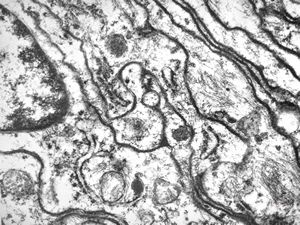

M,10y. | herpetic encephalitis